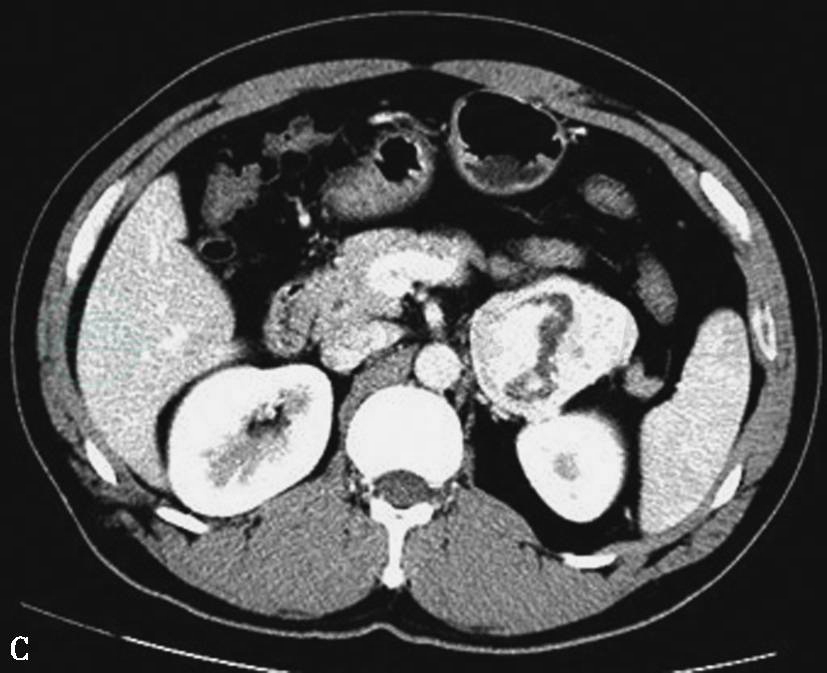

图13中央-边缘坏死

A~D.良性嗜铬细胞瘤不同形态及分布的坏死;E.左侧恶性嗜铬细胞瘤的伴中央-边缘坏死